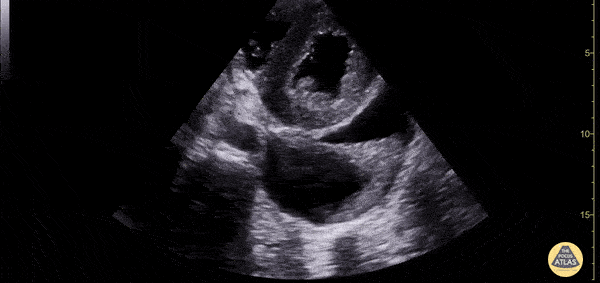

Patient with both a pericardial and pleural effusion in cardiac short axis view. You can see a large anechoic effusion surrounding the lung (pleural effusion) and a trace anechoic effusion spreading anterior to the descending aorta (pericardial effusion). Pleural effusions are never anterior to the aorta. Dimitri Livshits DO, Ultrasound Fellow, Kings County/SUNY Downstate; Jane Belyavskaya MD, Ultrasound Fellow, Kings County/SUNY Downstate; Chris Hanuscin MD, Ultrasound Division Director, Kings County/SUNY Downstate;